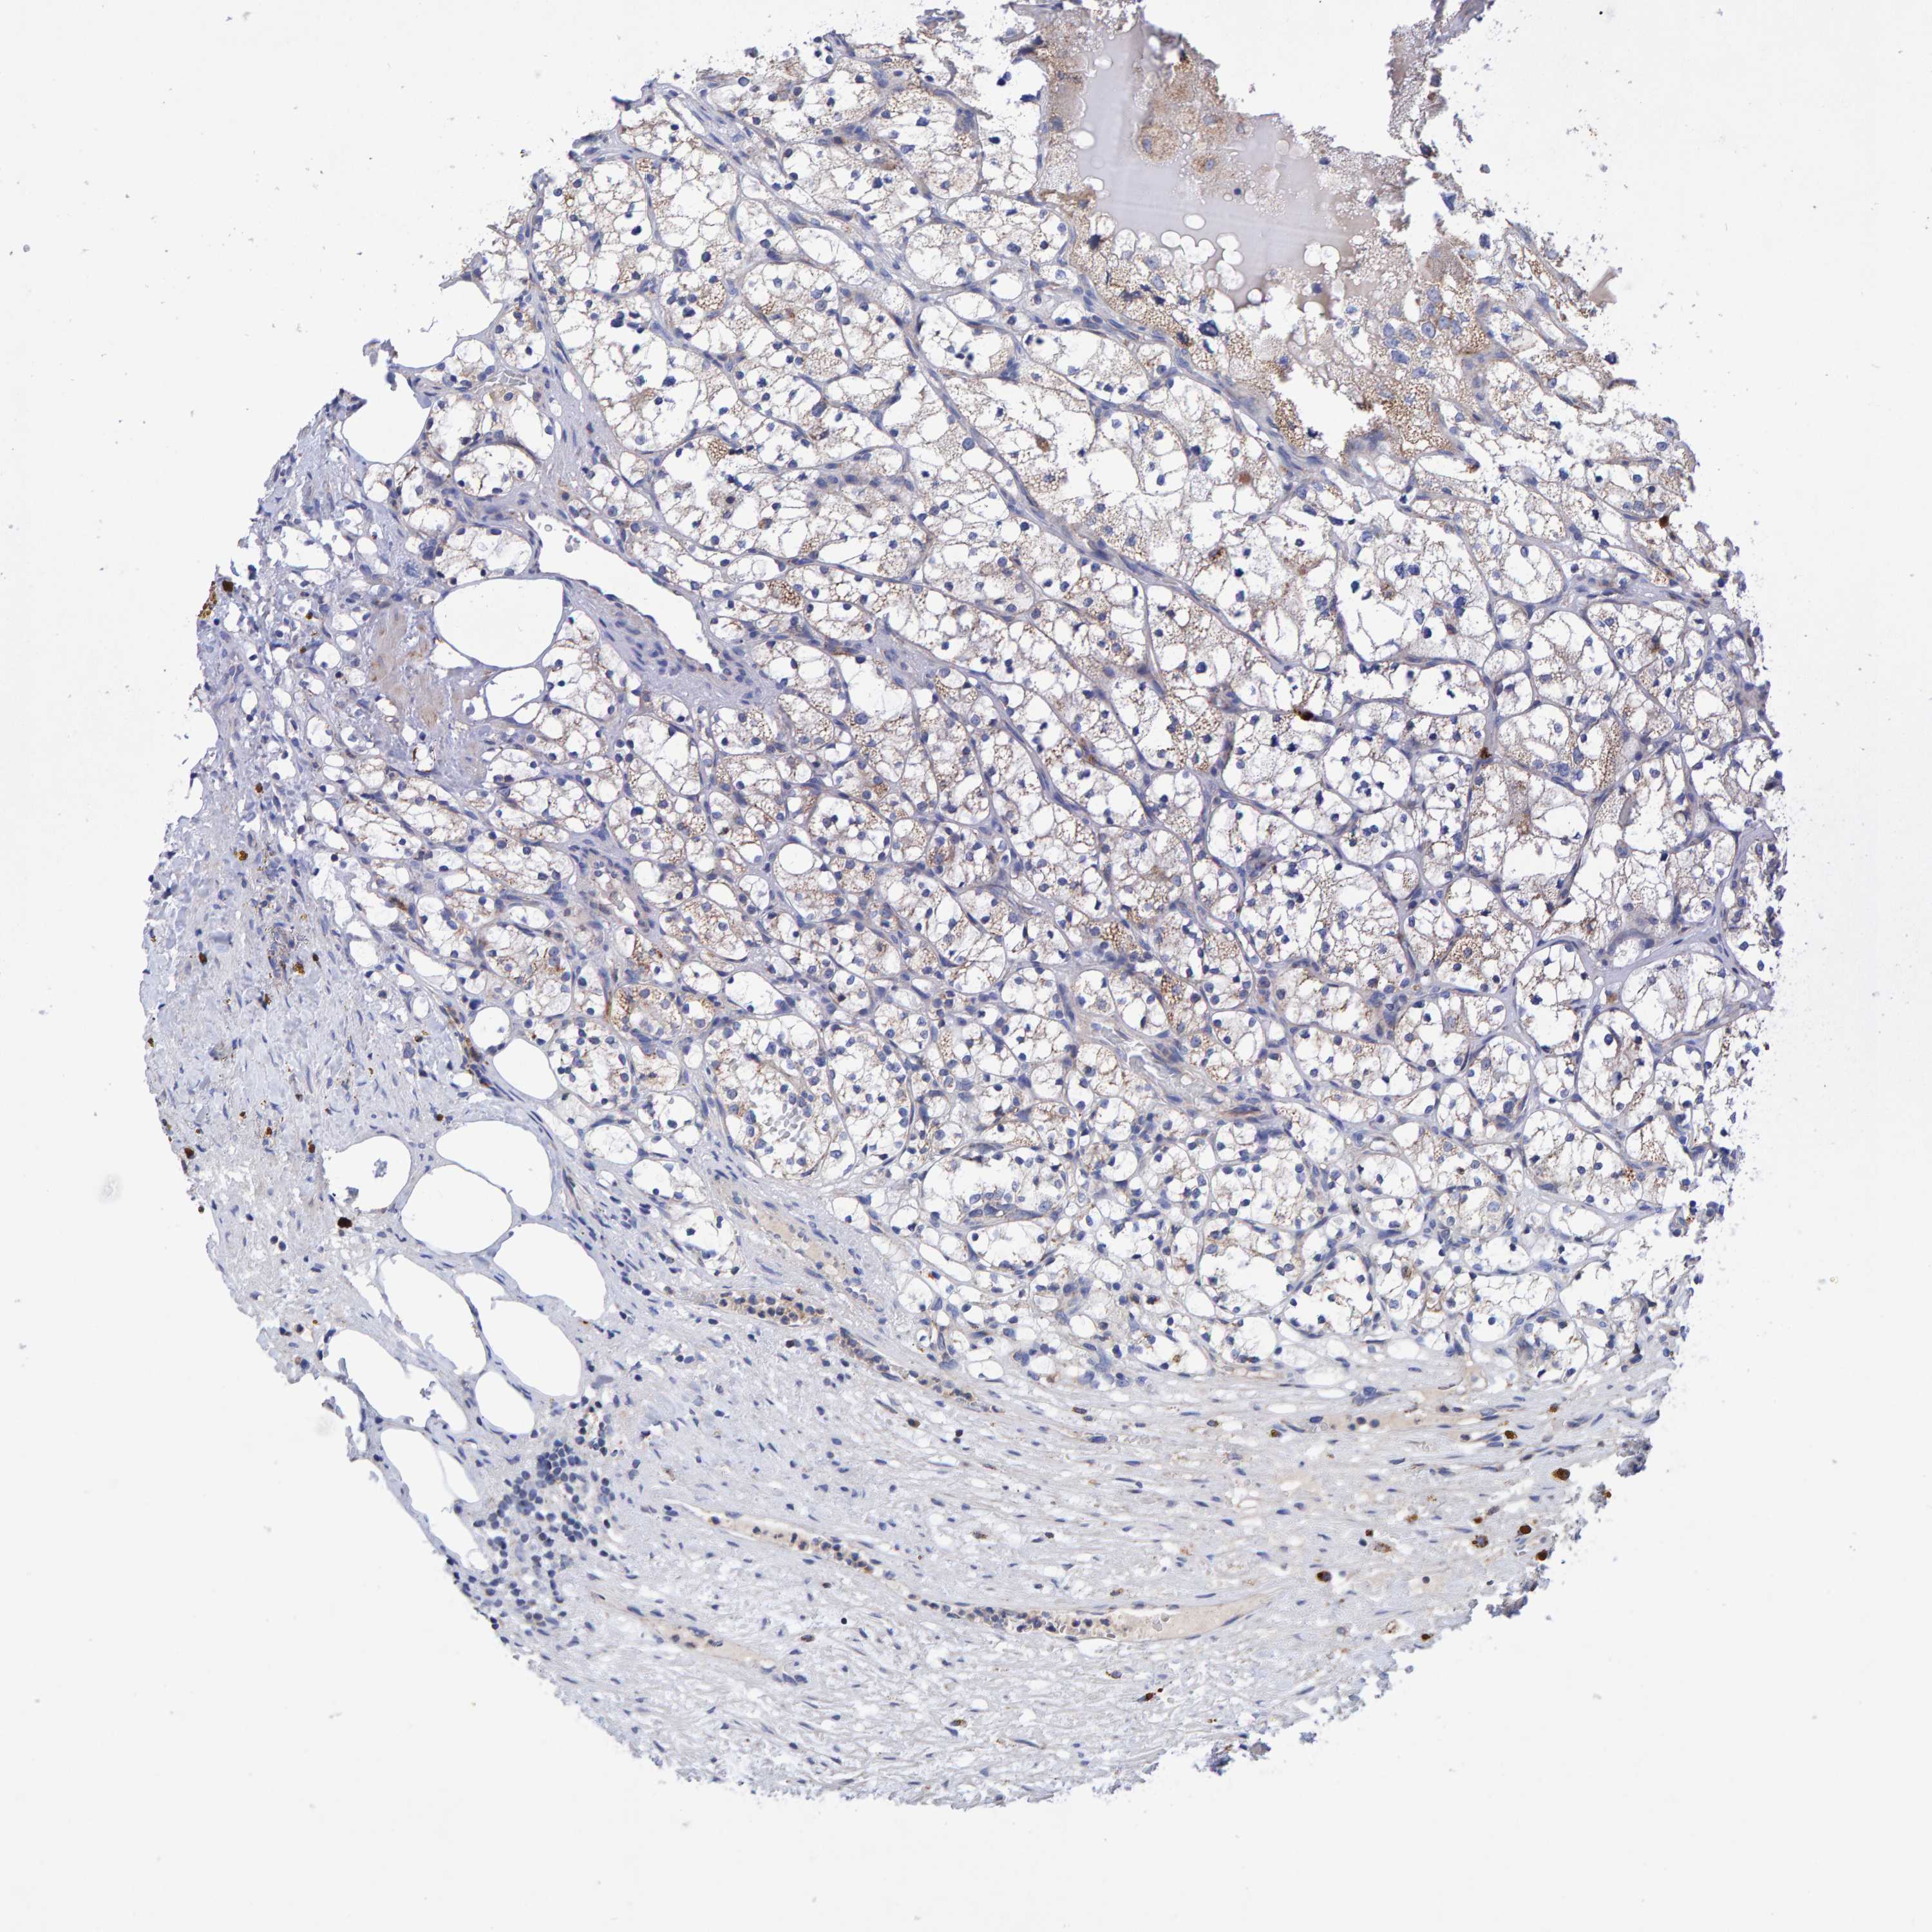

KIDNEY RENAL CLEAR CELL CARCINOMA (VALIDATION) - Interactive survival scatter ploti

The Survival Scatter plot shows the clinical status (i.e. dead or alive) for all individuals in the patient cohort, based on the same data that underlies the corresponding Kaplan-Meier plots. Patients that are alive at last time for follow-up are shown in blue and patients who have died during the study are shown in red.

The x-axis shows the expression levels (FPKM) of the investigated gene in the tumor tissue at the time of diagnosis. The y-axis shows the follow-up time after diagnosis (years). Both axes are complimented with kernel density curves demonstrating the data density over the axes. The top density plot shows the expression levels (FPKM) distribution among dead (red) and alive patients (blue). The right density plot shows the data density of the survived years of dead patients with high and low expression levels respectively, stratified using the cutoff indicated by the vertical dashed line through the Survival Scatter plot. This cutoff is automatically defined based on the FPKM cutoff that minimizes the p-score. The cutoff can be changed by dragging the vertical line or by entering a cutoff value in the square labeled "Current cut-off".

Under the Survival Scatter plot the p-score landscape (black curve; left axis) is shown together with dead median separation (red curve; right axis). Dead median separation is the difference in median mRNA expression between patients who have died with high and low expression, respectively. It is calculated as follows: median FPKM expression of dead patients with high expression - median FPKM expression of dead patients with low expression. This is intended to aid the user in visually exploring custom cutoffs and the associated p-scores and dead median separation.

Individual patient data is displayed and can be filtered by clicking on one or more of the category buttons on the top of the page. Categories describing expression level and patient information include: high, low, alive, dead, female, male and tumor stages. The scale of the x-axis can be toggled between linear and log-scale by clicking on the "x log" button. Mouse-over function shows TCGA ID, patient information and mRNA expression (FPKM) for each patient.

& Survival analysisi

Kaplan-Meier plots summarize results from analysis of correlation between mRNA expression level and patient survival. Patients were divided based on level of expression into one of the two groups "low" (under cut off) or "high" (over cut off). X-axis shows time for survival (years) and y-axis shows the probability of survival, where 1.0 corresponds to 100 percent.

EFR3A is not prognostic in Kidney Renal Clear Cell Carcinoma (validation)

Best expression cut offi

Based on the FPKM value of each gene, patients were classified into two groups and association between prognosis (survival) and gene expression (FPKM) was examined. The best expression cut-off refers the FPKM value that yields maximal difference with regard to survival between the two groups at the lowest log-rank P-value. Best expression cut-off was selected based on survival analysis .

When clicking on this number, the vertical dashed line indicating cut-off, the interactive survival plot, and the Kaplan-Meier curve will be adjusted to show results based on the best expression cut-off.

: 35.91

Median expressioni

Median expression refers to the median FPKM value calculated based on the gene expression (FPKM) data from all patients in this dataset. When clicking on this number, the vertical dashed line indicating cut-off, the interactive survival plot, and the Kaplan-Meier curve will be adjusted to show results based on the median expression.

: N/A

Median follow up timei

Median follow up time refers to the median time (years) after diagnosis with this type of cancer, based on clinical data from all patients in this dataset.

P scorei

Log-rank P value for Kaplan-Meier plot showing results from analysis of correlation between mRNA expression level and patient survival.

N/A

5-year survival highi

5-year survival for patients with higher expression than the expression cutoff.

For melanoma and glioma, 3-year survival is shown.

5-year survival lowi

5-year survival for patients with lower expression than the expression cutoff.

TCGA RNA samplesi

RNA-seq data is reported as average FPKM (number Fragments Per Kilobase of exon per Million reads), generated by the The Cancer Genome Atlas (TCGA) .

Normal distribution across the dataset is visualized with box plots, shown as median and 25th and 75th percentiles. Points are displayed as outliers if they are above or below 1.5 times the interquartile range. FPKM values of the individual samples are presented next to the box plot.

Average pTPM 35.3

Number of samples 100